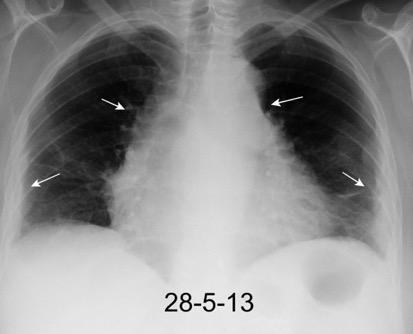

Carcinoma de mama con derrame pleural e implantes metastáticos

Makis W et al. Spectrum of Malignant Pleural and Pericardial Disease on FDG PET/CT. AJR. 2012